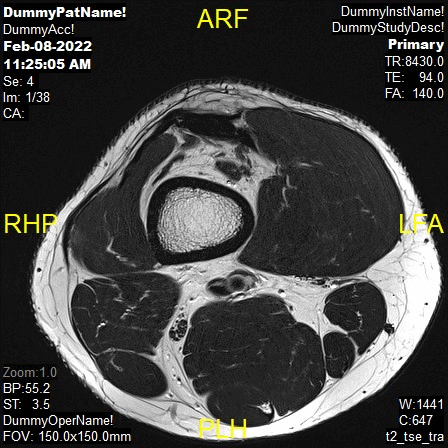

Sample Image